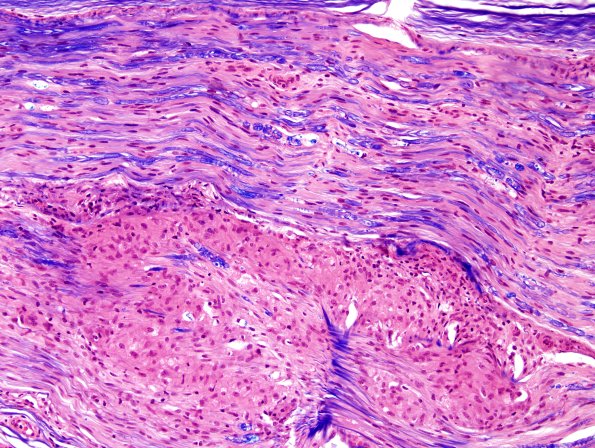

Additional longitudinal sections show axon loss and multiple granulomas. (H&E-LFB)